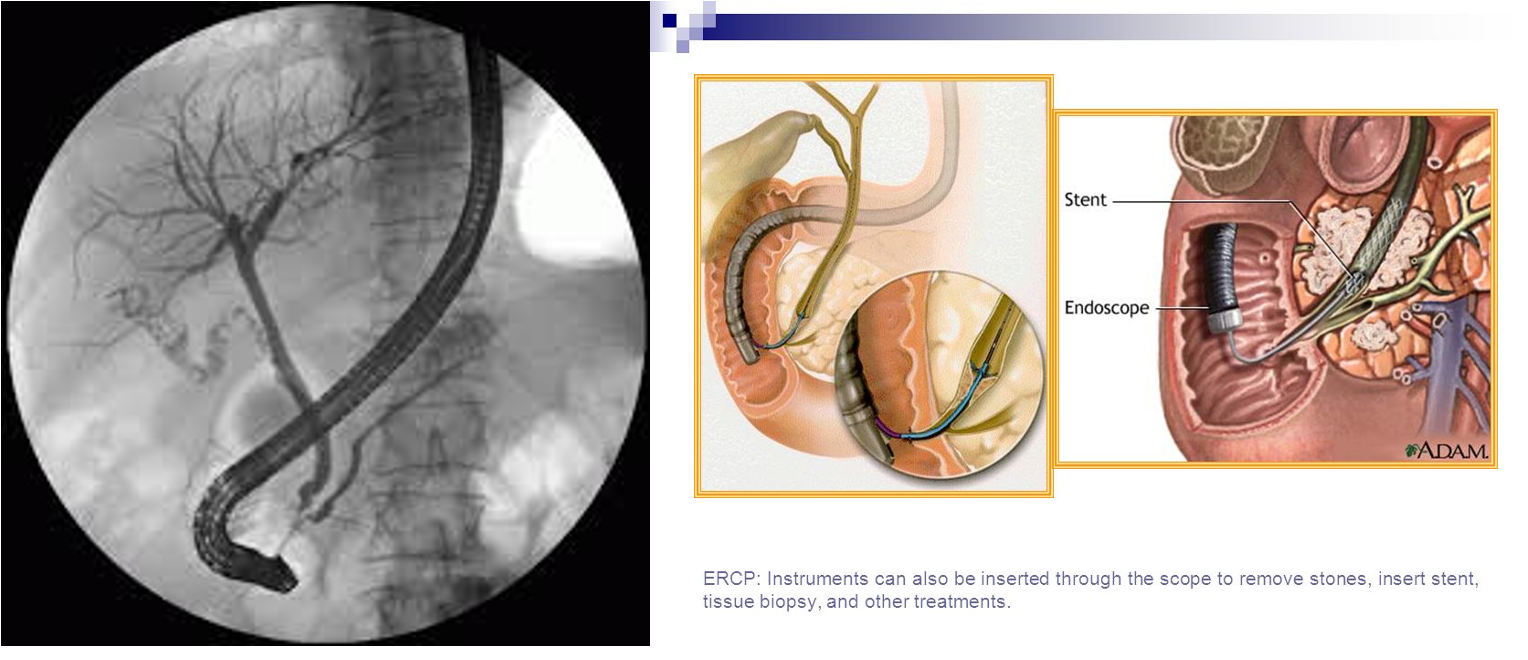

- Endoscopic retrograde cholangiopancreatography (ERCP) with stone extraction from the bile duct followed by laparoscopic cholecystectomy if the gallbladder containing stones.

Endoscopic retrograde cholangiopancreatography (ERCP)